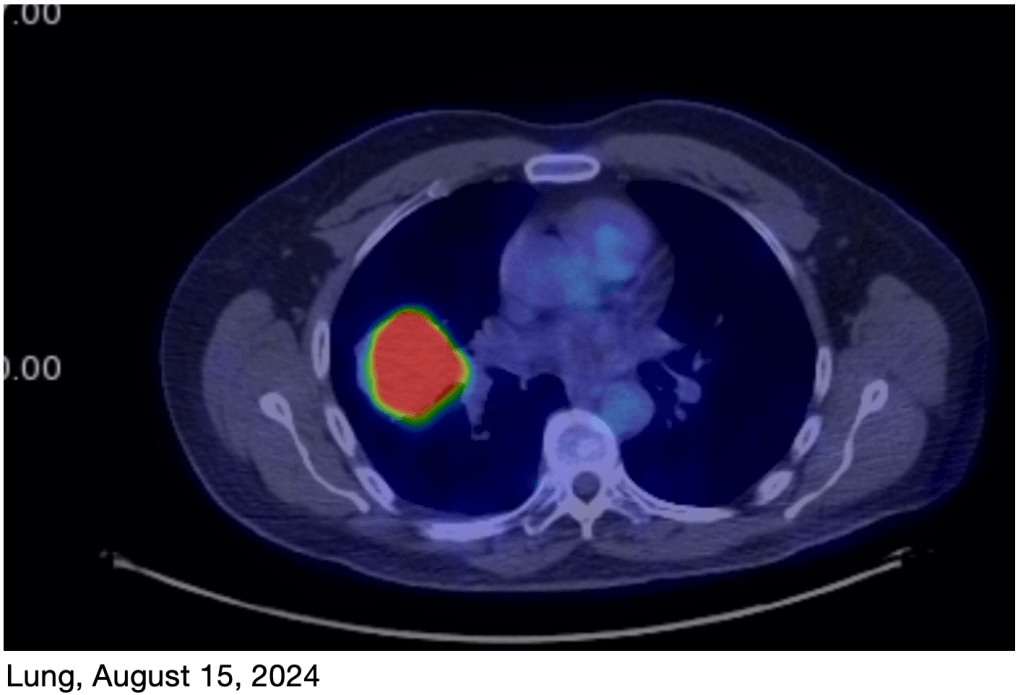

March PET Scan: I just had a new PET scan on Monday, and the results are great! The tumor on my rib is basically gone, and the primary tumor in my lung is now very small, just a faint reminder of what it was! This is obviously great news! I’ll have another scan in June.